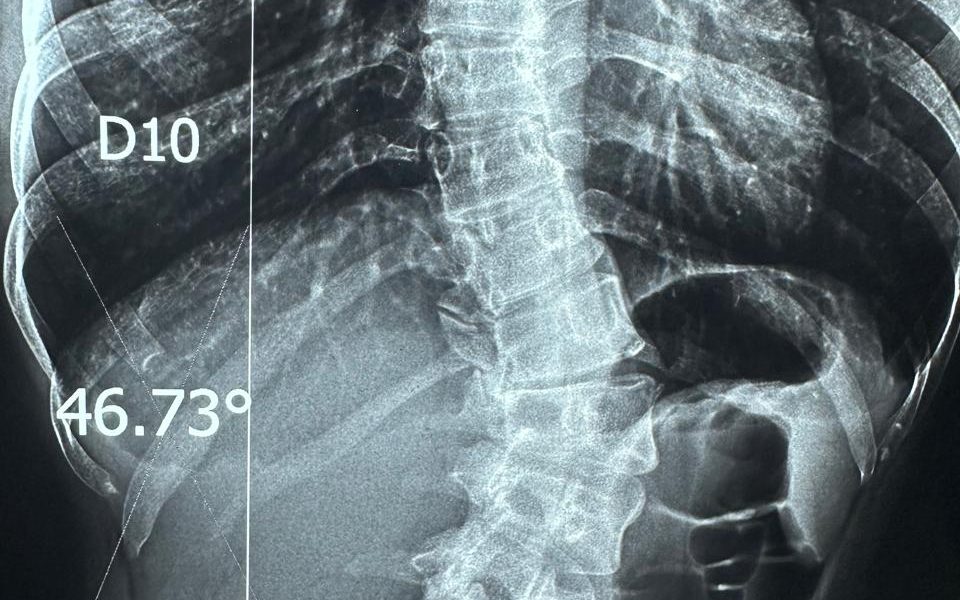

نجح الفريق الطبي بمستشفى قليوب التخصصي في تحقيق إنجاز طبي جديد، وذلك بعد تمكّنه من إجراء عملية دقيقة لمريضة كانت تعاني من اعوجاج شديد بالعمود الفقري، حيث تم إصلاح وتشريح الاعوجاج وتثبيت الفقرات باستخدام 20 مسمارًا معدنيًا لضمان ثبات واستقامة العمود الفقري.